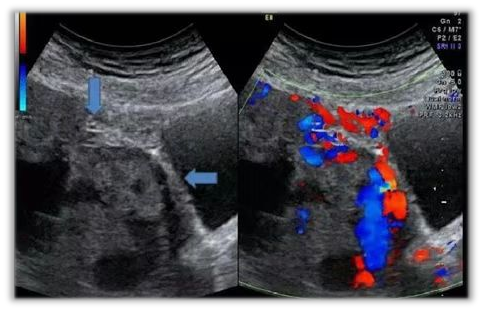

孕34周5天超声:胎盘位置:子宫下段的四壁(前、后、左、右侧壁),厚约7.7cm,胎盘下缘完全覆盖宫颈内口,胎盘内探及数个血窦回声,前壁下段胎盘与子宫肌层分界不清晰,胎盘后方探及异常丰富血流信号,子宫及膀胱浆膜层部分中断。宫颈长度约2.3cm,宫颈形态失常,宫颈内口处胎盘厚度约6.1cm,宫颈后唇探及血窦回声。

胎盘植入超声评分:12分(对胎盘植入凶险等级进行预测评分,评分≥10分,预测为穿透型胎盘植入)